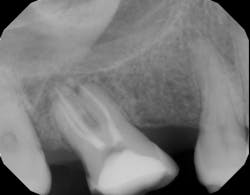

A periapical radiolucency is a hole in the bone formed as a result of inflammation under the root of the tooth as a means of housing the immune system to prevent the bacteria in the root canal from reaching the bone. It can be a precursor to a sinus tract (figure 1), which creates a path for drainage of inflammation into the oral cavity, rather than allowing it to spread through tissue planes.